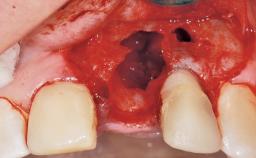

Immediate Placement of an Implant in a Maxillary Left Central Incisor Site

A 33-year-old female patient presented with an upper left central incisor that required extraction after a failed endodontic therapy. The tooth had been traumatized when the patient was a teenager and had undergone several endodontic treatments, including two apicectomy procedures. The patient was in good health and did not smoke. Clinical examination showed that the patient had a high lip line. In full smile, the gingival margins of the upper teeth were visible to the first molars. The gingival margins of central incisors 11 and 21 were only just showing. Examination of tooth 21 confirmed that the tooth was mobile and had hypererupted by 1 mm.

Soft Tissue Anatomy Intact Defective

Bone Volume Horizontally and vertically sufficient Horizontally deficient Deficient vertically or deficient vertically AND horizontally

Socket Integrity Damage to one or more bone walls

Bone Volume Damage to one or more socket walls